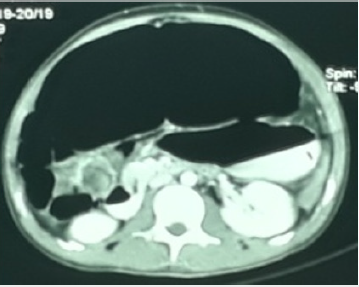

The focal rounded air-filled cecum may present as a loop with haustral markings resembling a coffee bean; which appears as a dilated bowel loop with an inverted “U” shape converging at the site of torsion, and a thickened central radiopaque line composed by the walls of the two part of the colon that are adjacent to each other. Doppler USG may lead to make a definite diagnosis by showing twisted mesenteric vessels [11], and CT may be more diagnostic by demonstrating cecal distension, cecal apex in left upper quadrant, mesenteric whirl, ileocecal twist, and small bowel distension [12]. An important sign to look for is the “whirl sign” that consists of a whirlpool pattern of swirling structures including collapsed bowel loops, mesenteric fat and engorged ileocecal vessels (Figure 3). This finding, associated to a dislocated enlarged cecum, is acknowledged to be diagnostic of volvulus [9,13]. The treatment of caecal volvulus preferred surgical procedure for the treatment of patients with cecal volvulus is right hemicolectomy [7].

Minimal soft stool was obtained on manual evacuation. Clinical diagnosis of Intestinal obstruction secondary to old abdomen surgery scar adhesions was made. Surgical opinion was obtained soon. Patient was then transferred to the surgical ward and urgent CT abdomen was requested. Large amount of impacted stool was removed on another manual evacuation of stool. A Ryle’s tube was inserted. No focal lung lesion in the lung bases. Mild left pleural effusion. There is hugely dilated bowel loop seen across the upper abdomen associated with whirlpool sign and small bowel loops seen at the right iliac fossa. Features are suggestive of cecal calculus. There is no bowel wall thickening to suggest bowel ischemia. However, there is mild free fluid seen in the abdomen and pelvis associated with streakiness of the mesenteric fat. The stomach and spleen are displaced by the dilated bowel loop posteroinferiorly. Faecal laden sigmoid colon and rectum noted. The descending colon and part of the transverse colon are collapsed with no bowel related mass seen. No focal lesion in the liver, spleen, adrenals and pancreas. No hepatosplenomegaly. The CBD and intrahepatic ducts are not dilated. There is no calculus in the gall bladder. Both kidneys have normal enhancement. No hydronephrosis. No significant para aortic or pelvic lymphadenopathy. No suspicious bony lesion.

Features are suggestive cecal volvulus with mild free fluid. Mild left pleural effusion.

In our opinion this patient seems to be suffering from double pathology: Chronic large bowel obstruction due to post-op adhesion, and Cecal Volvulus due to congenital predisposing factors. Radiology plays a role to diagnose caecal volvulus since there is no specific symptoms and signs of caecal volvulus except those of intestinal obstruction. There were classic plain X-ray abdomen of coffee bean sign of caecal volvulus [8-10] and CT abdominal features of caecal volvulus [12,13] in this patient. Mildly low sodium level and high urea changes indicate dehydration due to bowel obstruction. An elevated white blood cell (WBC) count may indicate bowel ischemia, peritoneal infection with or without gut perforation, or systemic sepsis. However, there was no features of sepsis clinically in this patient preoperatively. Therefore, bowel ischemia is the most likely cause of leukocytosis in this case preoperatively. Different treatment and results are reported by Consorti ET and Liu TH [1]: Barium enema sporadic reports of reduction after barium enema. The success rate is unknown. This modality is not usually recommended as a therapeutic option.